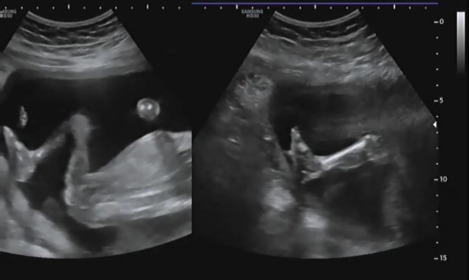

허벅지 길이를 측정하고 아래를 보면 발가락의 개수를 확인했다. 양측 모두 다 발가락 5개 있는지 확인했다. 초음파를 보는데 햇님이가 불편한지 여기저기 발로 밀어대는 모습을 볼 수 있었다.

그다음 손가락을 확인하는데 발도 너무나 귀여웠지만 손을 확인할 땐 더욱 귀엽다고 생각했다. 양쪽 손 모두 손가락 5개 있는 것을 확인하는데 햇님이가 주먹을 쥐고 잘 안 보여줬다. 의사가 나의 배를 살며시 흔들어 햇님이의 반응을 보니 그제야 손을 펴 손가락 5개임을 확인시켜줬다.